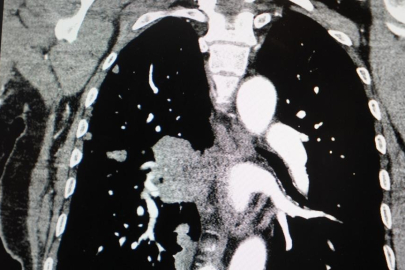

Akciğer kanseri vakalarındaki artışa da dikkat çeken Özkaya, "Son yıllarda hem sigara içen hem de hiç sigara kullanmamış bireylerde akciğer kanseri vakalarında dikkat çekici bir artış görüyoruz. Özellikle kadınlarda adenokarsinom tipi akciğer kanseri belirgin şekilde artış göstermektedir., Yapılan son araştırmalara göre akciğer kanseri teşhislerinin yaklaşık yüzde 20'si hiç sigara içmemiş bireylerde konuluyor. Bunun en önemli nedeni pasif içiciliktir. Yani siz sigara içmeseniz bile, yakın çevrenizde sigara içiliyorsa akciğer kanseri riskiyle karşı karşıya kalabilirsiniz" ifadelerini kullandı.